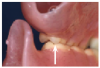

Contact is limited to the lingual cusps of the upper posterior teeth.

Figure 20

Figure 21

Patients are instructed to push food

posteriorly when incising.

Figure 22

Figure 15 shows a situation with extensive bone loss in both arches. Sinus grafts in the upper arch and implants placed in the grafted sites failed, leaving bilateral oral-antral communication. Revision surgery attaching the buccal mucosa to the residual ridge closed the oral-antral communications, leaving a flat residual ridge with very limited topography (Figure 16). Limited residual bone in the lower ridge determined the asymmetrical location of five implants to provide a screw-retained, implant-supported prosthesis (Figure 17). The residual maxillary posterior ridge crests are medial and posterior the lower arch, opposing a lower implant-retained prosthesis with a Class III relationship to the lower ridge (Figure 18). A lingualized occlusal scheme was designed to limit upper posterior lingual cusp contact to the central fossa of the lower posterior teeth more medial than usual, especially on the lower left side, to stabilize the relatively unstable upper denture (Figure 19). Contact between anterior teeth is avoided during vertical closure while chewing (Figure 20 and Figure 21). Patients are instructed to push food being incised posteriorly against the upper denture to avoid dislodging it, instead of pulling the food forward, as with normal dentitions. Pushing posteriorly seats the denture against the palate (Figure 22).